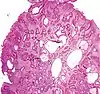

| Juvenile Polyp | Upper GI tract and colon | Cystically dilated glands with expanded lamina propria | Not inherently, may develop dysplasia |  |

Juvenile polyposis syndrome, identical polyps in Cronkhite–Canada syndrome |